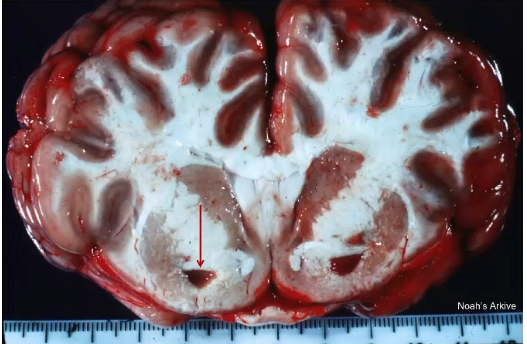

what type of hemorrhage is this?

parenchymal hemorrhage, CSF tap gone bad